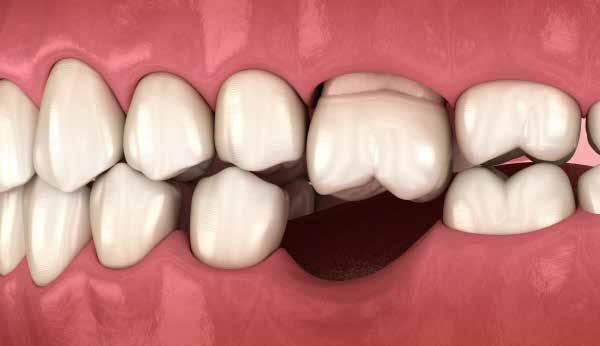

frontfogak esztétikailag is kellemetlen megjelenést biztosítanak, ugyanakkor mivel a frontfog stop nem elégséges, így az állkapocs előrecsúszását eredményezi, majd a fogak a nagymetszőkön támaszkodva további funkcionális problémát is okoznak. A fogérintkezés problémái az izomzatban is jelentkeznek, a kompenzációk szinte azonnal láthatók az arcon, később a test izmain, a testtartáson is. Különböző fogérintkezési problémák izomkompenzációs mintázata teljesen típusos megjelenésű, leolvasható a testtartásból, sőt az arcról is.

rotáció esetén például a bal oldali maxilla fogazat kifelé dől és intrudálódik, a jobb oldali maxilla fogazat befelé dől és elongeálódik (10. a-b kép);